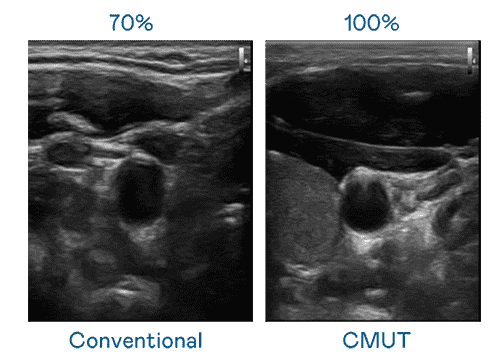

CMUT 技术是一种用电容式微机电元件来产生超音波讯号的技术。。。。与传统 PZT 压电式技术相比,,CMUT 频宽增加 30%,,,更宽频的超音波讯号让影像解析度大幅提升,,,,是实现高影像品质医疗超音波扫描、、、促进精准医疗发展的关键技术。。

大频宽带来超清晰影像

超音波影像的解析度高低,,首先取决于探头能发出的讯号频宽。。菠菜论坛 CMUT 可提供高清晰的超音波讯号,,,,提供高频宽、、、、高灵敏度、、、影像纹理细节更高的超音波影像,,协助医护人员缩短影像判读时间及利用精准的医疗影像进行诊断。。。。